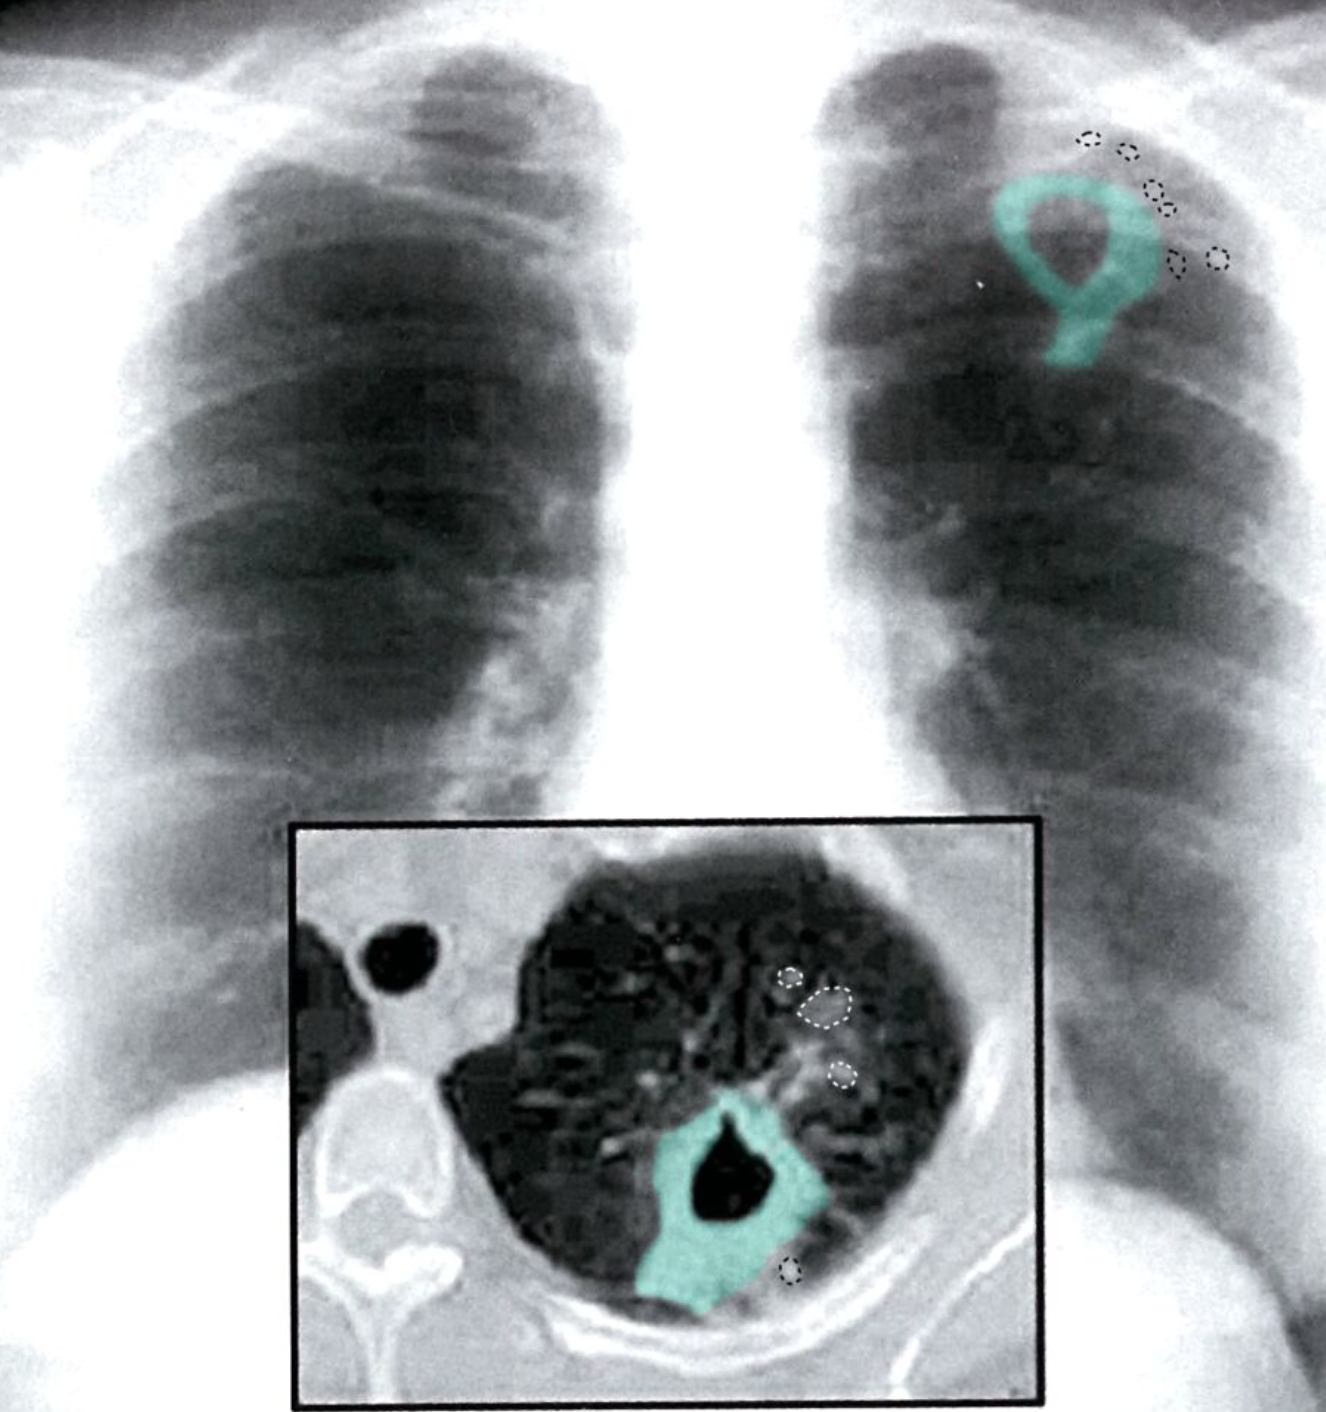

Cavitary lung lesion

X-ray chest (PA view; insert: axial CT, lung window) of a patient with postprimary tuberculosis

A thick-walled irregularly shaped cavity (green overlay) in the left lung apex is surrounded by micronodular opacities (examples indicated by dotted lines), which are better seen on the CT image than on the chest radiograph.

The differential diagnosis for a cavitary lung lesion includes both infectious (bacterial, fungal, and occasionally parasitic) and noninfectious (malignant, inflammatory, vascular, and traumatic) etiologies. In postprimary tuberculosis, the apicoposterior segments of the upper lobes and superior segments of the lower lobes are common sites of involvement. A thick-walled cavity accompanied by consolidation or nodular opacities can signify active disease